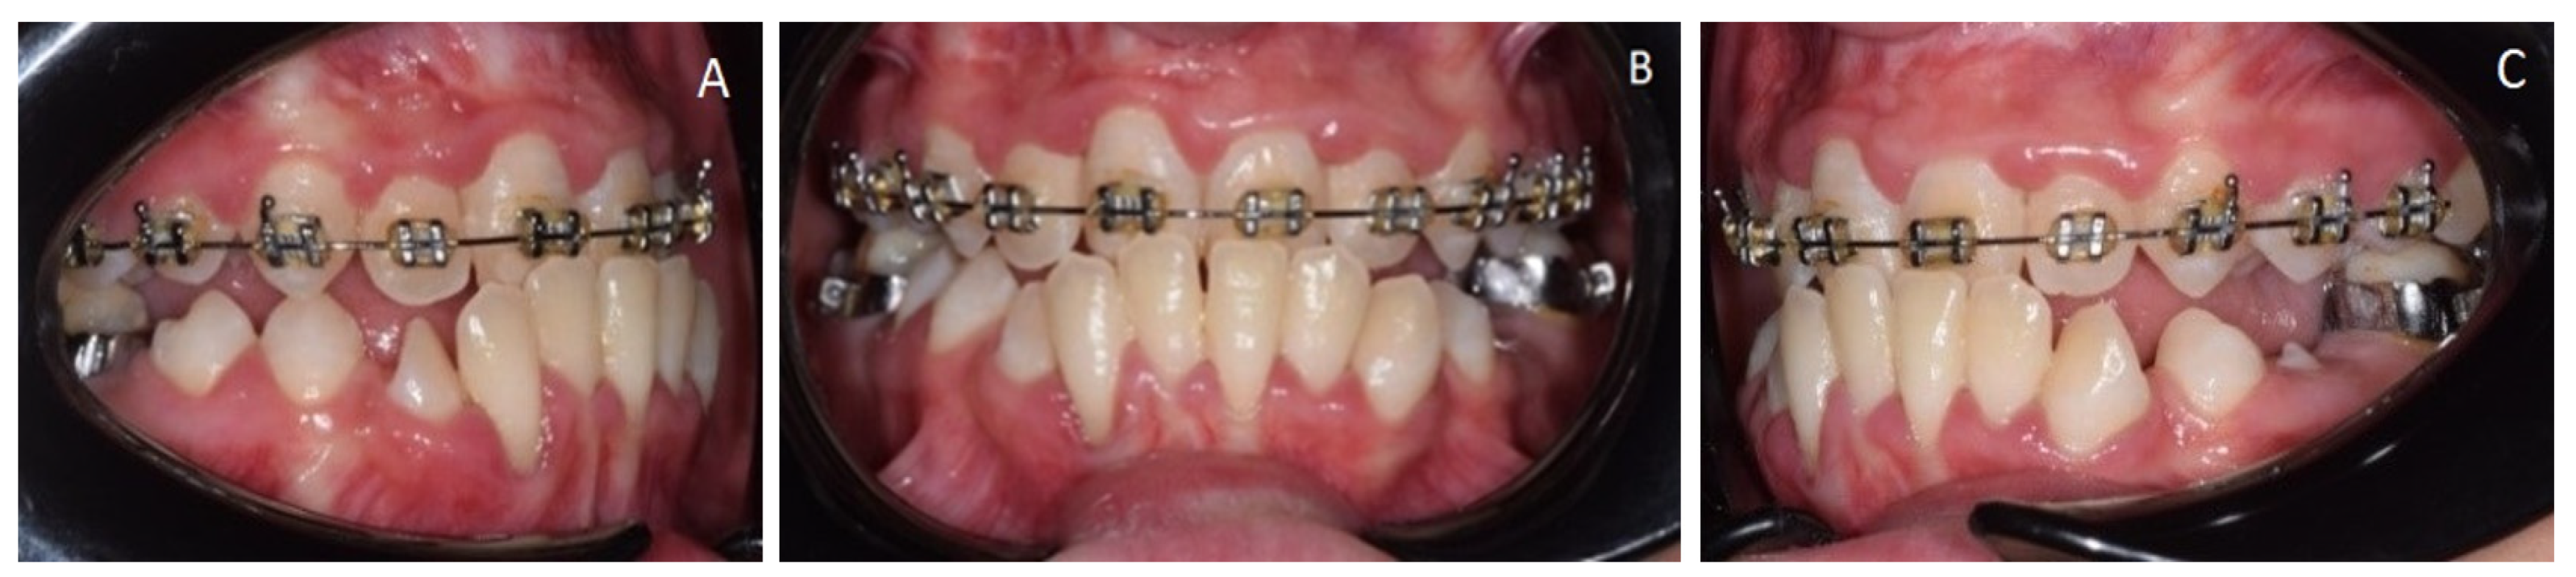

2. Clinical Report

2.2. Considerations for Supranumerary Teeth Extraction